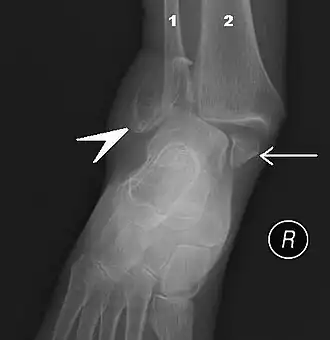

![]() Правый голеностопный сустав, вид сбоку. | |

В ходе объективного обследования применяются физикальные методы исследования: осмотр, пальпация. Немаловажное значение имеет тщательный сбор анамнеза. Из инструментальных методов большое распространение получило рентгенологическое исследование голеностопного сустава в прямой, боковой, а также косой проекции. В настоящее время для диагностики применяют также артроскопию.